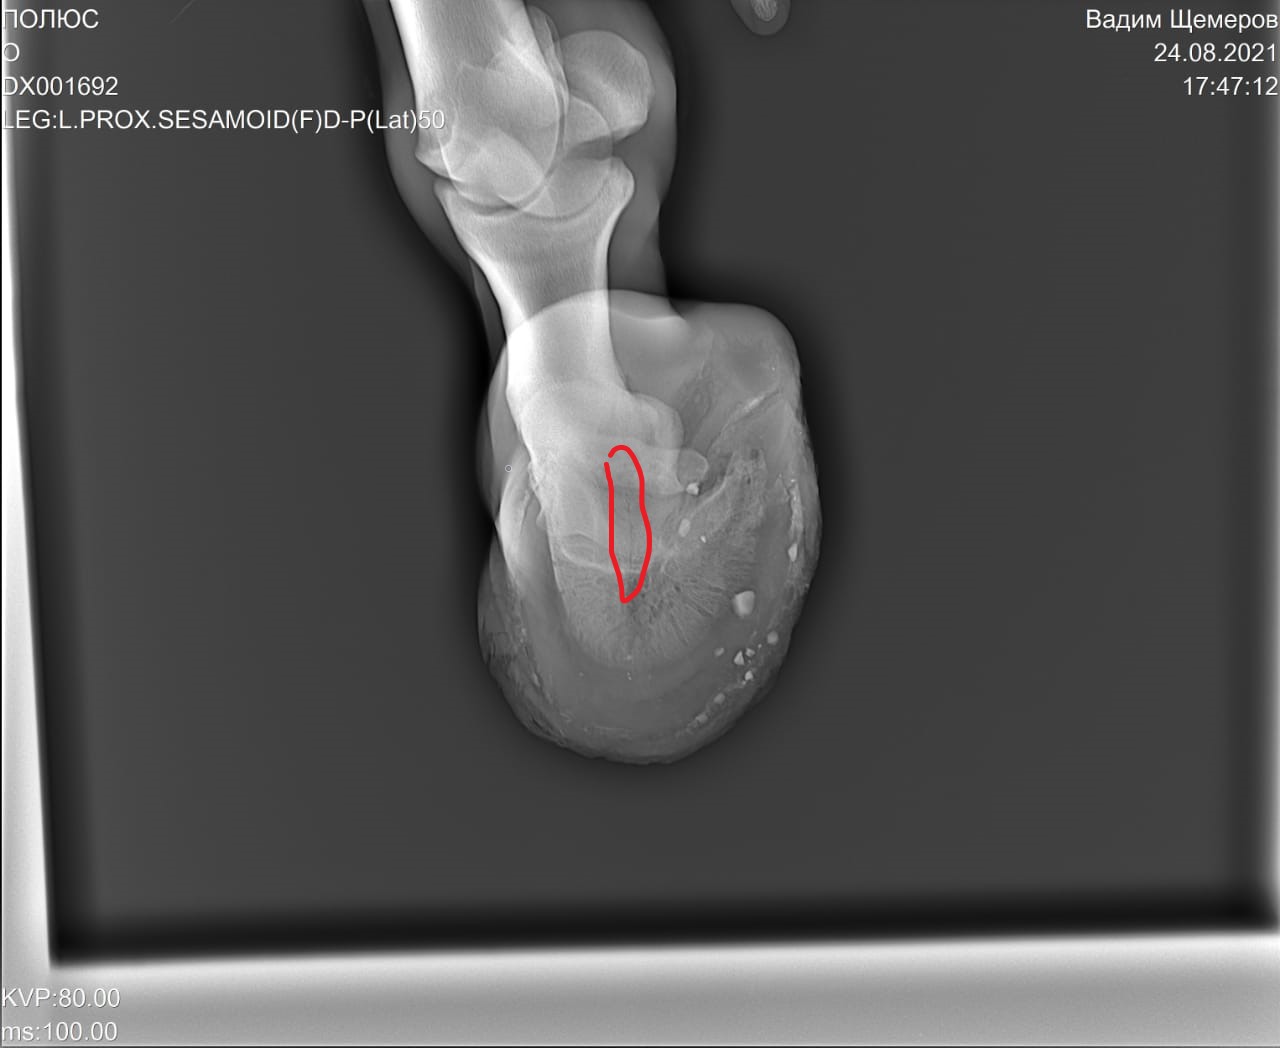

На рентгеновских снимках выявлено:

1) остеохондроз и чип в области путового сустава правой грудной конечности.

2) Старый перелом и изменение конфигурации края челночной кости с переостальной реакцией этого края.